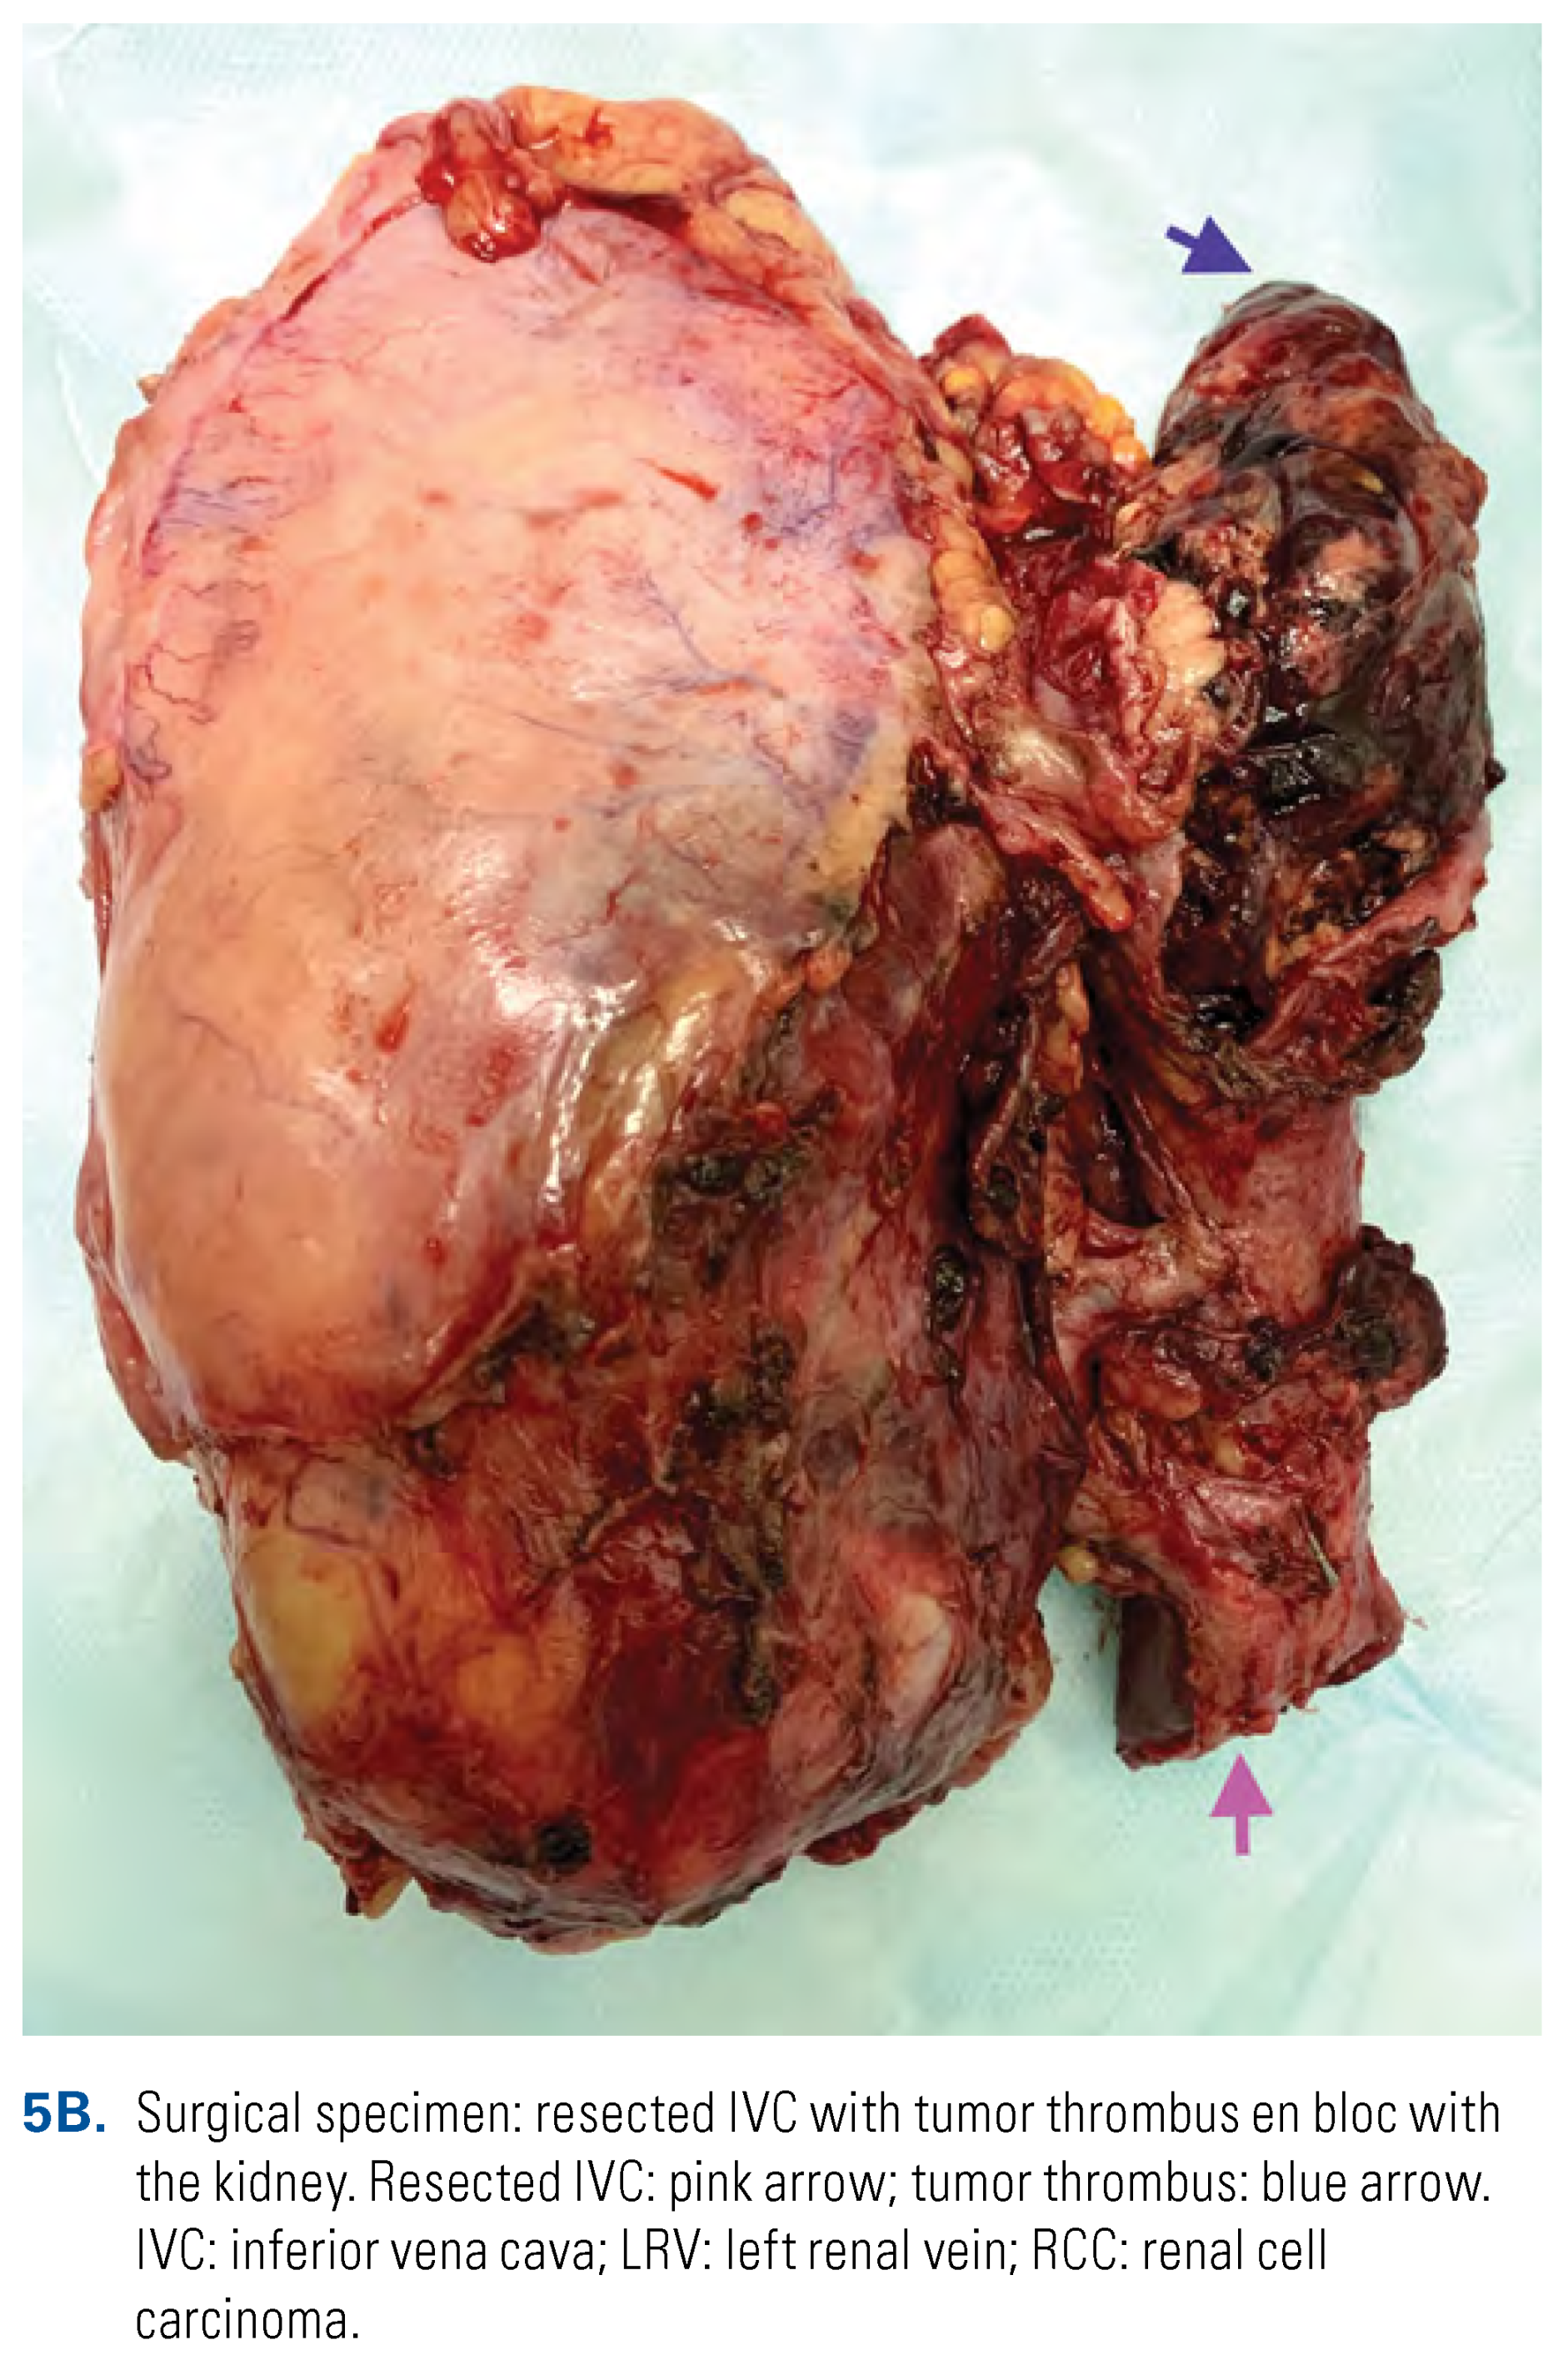

Thrombectomy in Patients with Tumor IVC Wall Invasion and/or Descending Bland Thrombosis